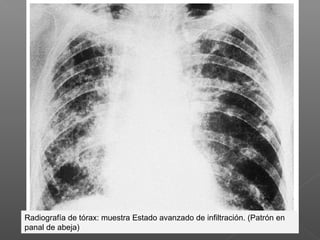

Radiografía de tórax: muestra Estado avanzado de infiltración. (Patrón en

panal de abeja)